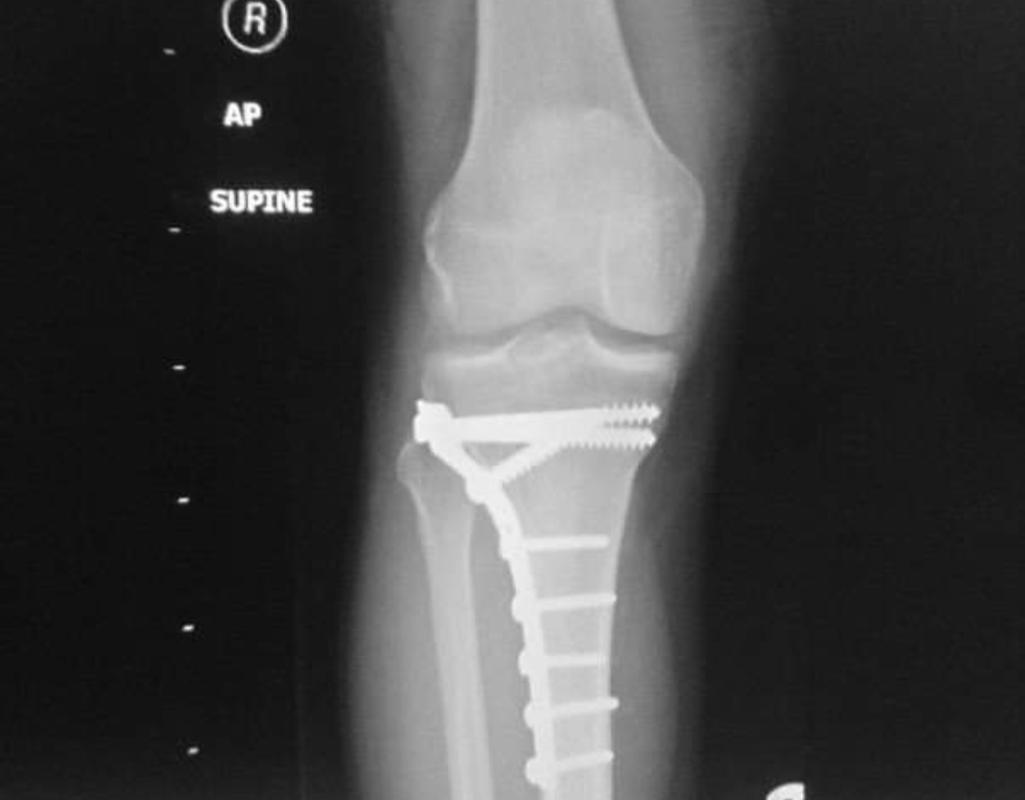

Anyway I've been to A&E and the fracture clinic and they've put me in a cast and I'm waiting for an MRI. The consultant I saw yesterday said I have a week window to reconstruct the knee and need the MRI first. They can see from the X ray that I've pulled away the bone where the LCL attaches to the fibia

Big metal plate and lots of what look like poorly sized ring shank screws still in place. Doesn't look quite as bad as Kayaks mind.

Ended up 2 weeks from fracture to surgery resulting in a required more work to reposition the break, and similar hardware to those xrays above.